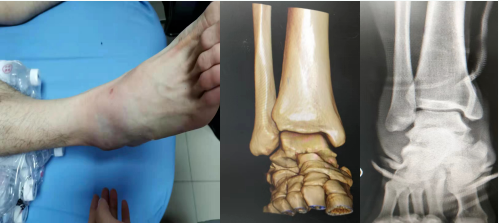

送到我院后,急诊医生立刻安排检查,X线片和CT检查提示:距骨周围脱位!

X线片和CT图片